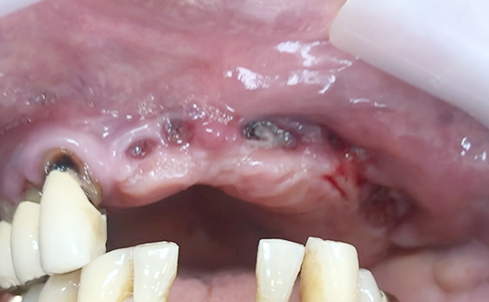

Fully edentulous clinical cases